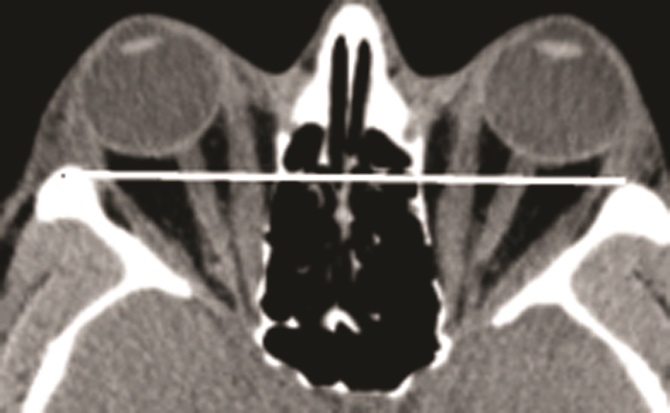

Рис. 4. Липогенный вариант эндокринной офтальмопатии. б — МСКТ орбит, аксиальная проекция (глазные яблоки расположены выше межскуловой линии – белая линия).

Основной характеристикой «липогенного» варианта является отсутствие увеличения ЭОМ при выраженной пролиферации РБК. Липогенный вариант протекает более доброкачественно [10]. Несмотря на выраженный проптоз и периорбитальные отеки, движения ЭОМ сохраняются в полном объеме. У больных с липогенным вариантом редко наблюдаются оптическая нейропатия (ОН), изменение глазного дна, ухудшение остроты зрения и цветового зрения, так как отсутствует компрессия ЗН в области вершины орбиты. Липогенный вариант подтверждается различными методами визуализации, которые не выявляют или выявляют очень умеренное утолщение ЭОМ (рис. 4 на цв. вклейке, см. раздел Дополнительная информация). При исследовании рентгеновской плотности ЭОМ выявляются гиподенсные участки, которые приближаются по плотности к жировой ткани (от 0 до –36 HU).

Увеличение ЭОМ и (или) РБК может приводить к возникновению экзофтальма (проптоза). Установить причину экзофтальма можно с помощью визуализирующих методов исследования [9]. Вовлечение в процесс ЭОМ обнаруживается при МСКТ у большинства пациентов. Увеличение объема РБК при нормальных размерах мышц или их незначительном увеличении наблюдается значительно реже. По нашим данным, увеличение РБК без увеличения ЭОМ, так называемый «липогенный» вариант ЭОП, наблюдается у 20% пациентов с ЭОП, увеличение ЭОМ без увеличения РБК («миогенный» вариант) у 11%. В остальных 69% случаев ЭОП имела типичный характер с вовлечением в процесс как ЭОМ, так и РБК.